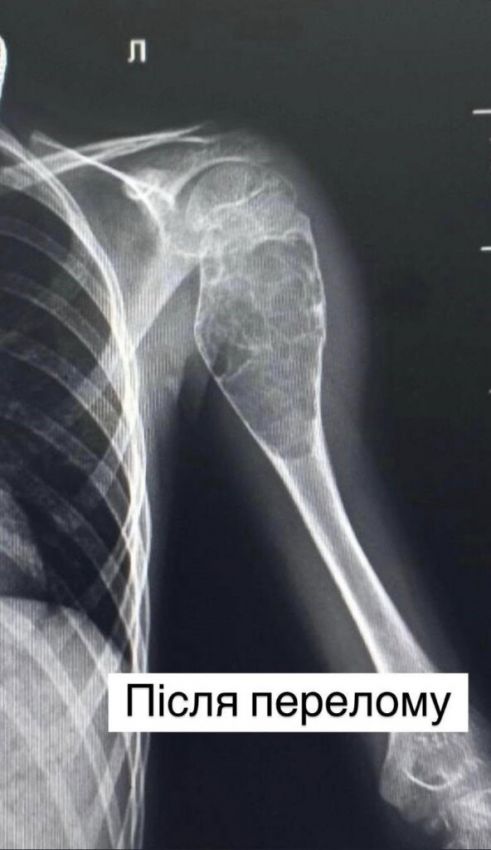

Все почалося в 2022 році, коли хлопчик впав під час збирання грибів. У лікарні наклали гіпс. Та незабаром ситуація повторилася – загалом у Івана було 8 переломів у тому самому місці – лівій плечовій кістці.

Однак наполегливість та цілеспрямованість матері врятувала Івана. Вона після пошуків у інтернеті та за порадами знайомих звернулася до фахівців львівського Охматдиту. Проведені рентген-знімки в динаміці показали: часті переломи спричинені пухлиноподібним утворенням у кістці.

Після усіх обстежень ортопеди-травматологи лікарні провели складну операцію: виконали внутрішню кісткову резекцію – видалили пухлину розміром 9 см на 4 см та замістили дефект кістковими аллотрансплантатами. А також провели металоостеосинтез кістки двома гнучкими титановими стержнями, щоб уникнути повторних переломів. У післяопераційному періоді рука дитини була іммобілізована тільки косинковою пов’язкою, без використання важкої та громіздкої гіпсової пов’язки.

“Кістка була настільки розм’якшена, що буквально провалювалася під невеликим натиском. Ще трохи – і вона могла б зруйнуватися повністю”, – розповідає ортопед-травматолог Олег Токай.

Матеріал пухлини передали на гістологічне дослідження для детального аналізу та встановлення остаточного діагнозу. Гістологія підтвердила, що це аневризмальна кіста.